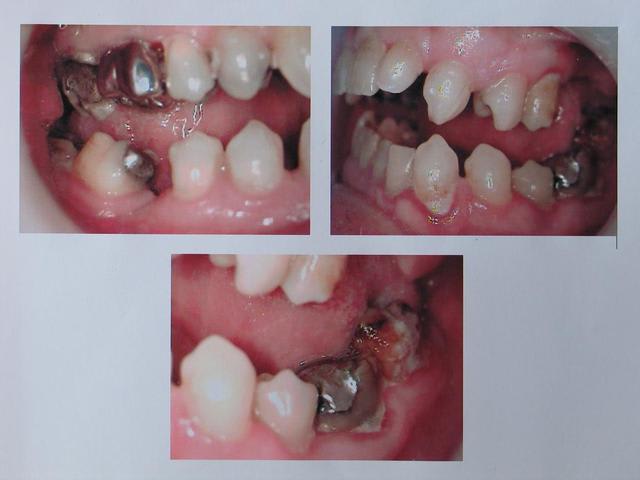

patient vu en consult pour aphtes récurrent ( tous les mois ) : apparition d'une sensibilité vers 17, qui gagne l'ensemble de la bouche, puis survenu des aphtes.

L'occlusion est a chier, avec endomaxillie, déviation des milieux, inversé d'articulé à gauche, mais pas de trouble ATM

Le contrôle de plaque est pas terrible, il y a une parodontite chronique ( amibe, bâtonnet ++ , PN ++ ). Le plan de ttt est d'extraire 37, de traiter la parodontite, de couronner ce qu'il faut, mais quand est-il de sa demande initial ?

Les aphtes : est-ce que le traitement de la paro va améliorer les choses ?